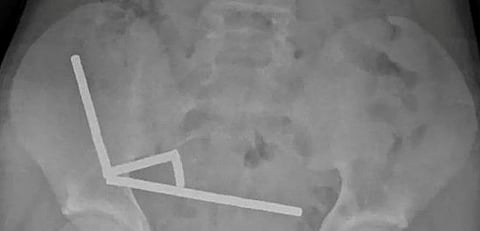

ورغم حظر هذه المغانط في نيوزيلندا منذ يناير 2013، أفاد الأطباء بأنها تم شراؤها من منصة التسوق "تيمو". وأظهرت الأشعة السينية تجمع المغانط في أربع خطوط مستقيمة داخل الأمعاء، حيث ظهرت في أجزاء منفصلة التصقت ببعضها بسبب القوى المغناطيسية، ما تسبب بضغط أدى إلى نخر في أربع مناطق من الأمعاء الدقيقة والأعور.